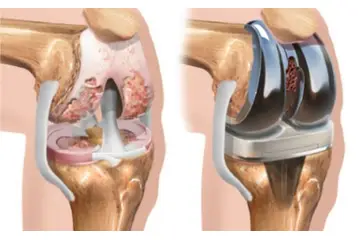

Diz Kıkırdak Belirtileri ve Tedavisi Diz kıkırdağı, diz ekleminin düzgün çalışabilmesi için kritik bir yapı oluşturur. Kıkırdak, eklem yüzeylerini kaplayarak sürtünmeyi azaltır ve hareket sırasında şok emici bir görev üstlenir. Ancak, çeşitli nedenlerden dolayı diz kıkırdağında hasar meydana gelebilir. Bu yazıda, diz kıkırdağında oluşabilecek belirtiler, bu belirtilerin nedenleri ve tedavi yöntemleri detaylı bir şekilde ele alınacaktır. Diz Kıkırdak Hasarının Belirtileri Diz kıkırdağında meydana gelen hasar, çeşitli belirtilerle kendini gösterebilir. Bu belirtiler, hasarın ciddiyetine ve nedenine bağlı olarak değişiklik gösterebilir. Yaygın belirtiler şunlardır:

Diz Kıkırdak Hasarının Tedavi Yöntemleri Diz kıkırdak hasarının tedavisi, hasarın ciddiyetine ve bireyin genel sağlık durumuna bağlı olarak değişir. Tedavi yöntemleri arasında şunlar bulunmaktadır: